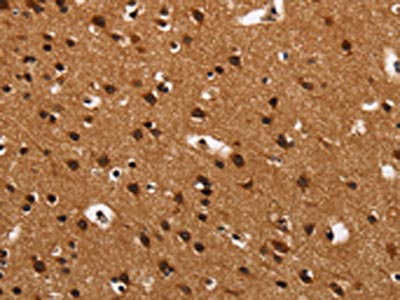

The image on the left is immunohistochemistry of paraffin-embedded Human brain tissue using CSB-PA695075(ARSB Antibody) at dilution 1/50, on the right is treated with synthetic peptide. (Original magnification: ×200)